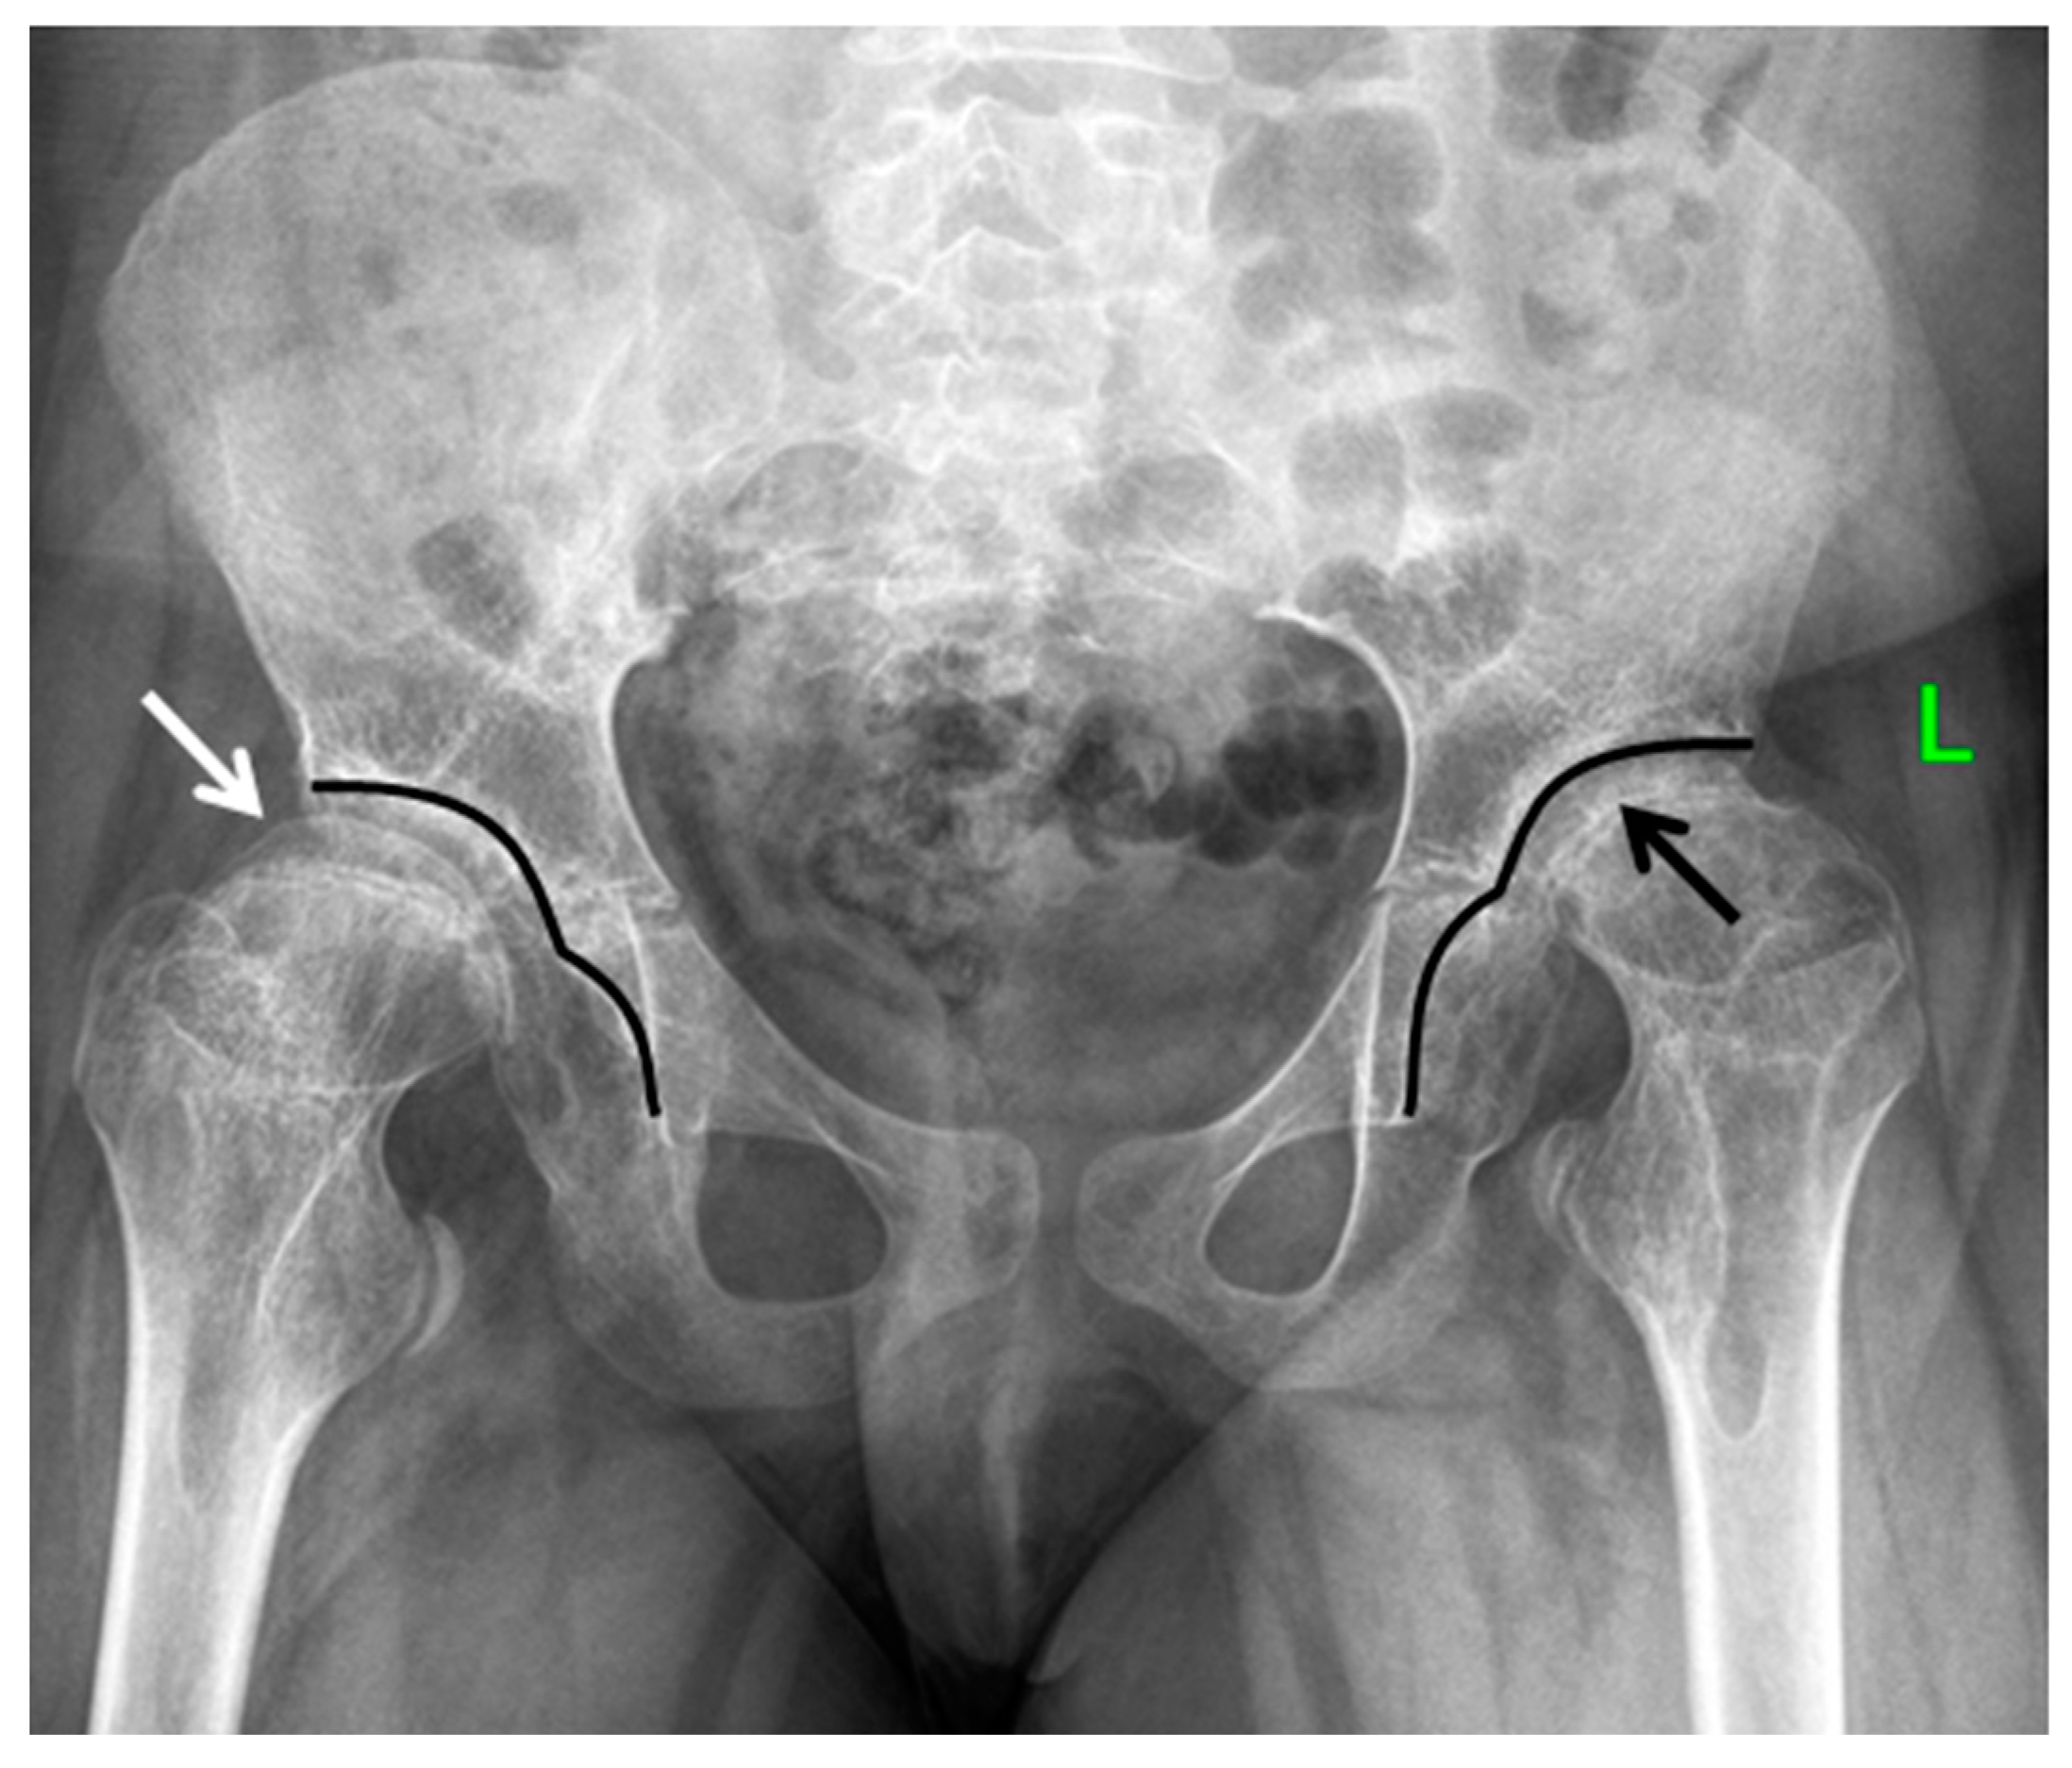

The most prominent radiological manifestations included the deformities of the femoral heads (Figure 4). In most of the cases, the first changes were detected symmetrically on both sides, although in some cases, there was an asymmetry of manifestations, which led to the misdiagnoses of the local pathology of the hip joints: Perthes disease, avascular necrosis of the femoral head, or sequelae of septic arthritis (Figure 5).

Most of the epiphyses of the long tubular bones at a young age were characterized by a decrease in the size of the ossification nuclei, which, as the child grew, was transformed into a decrease in epiphyseal height (flattening and elongation along the line of the metaphysis, its radiographic appearance resembling the mushroom-shaped or half-moon-shaped epiphysis). A widening of the metaphysis of the long tubular bones was also noted. For the proximal femur, this resulted in the widening and shortening of the femoral necks, leading to the so-called cervical coxa vara or the coxa breva. From the biomechanical point of view, this shortening leads to the shortening of the lever arm of the hip abductors (the gluteus medius muscle)—the main frontal stabilizer of the hip joint—and as a result, to the main clinical pattern of gait disturbance in this disease, namely the waddling gait (or Trendelenburg gait) and/or the swaying of the trunk when walking (Duchenne phenomenon). As the child grew, the clinical and radiological picture was accompanied by advanced signs of osteoarthritis of the hip and knee joints, which were seen in all patients of the studied group to some extent during their observation (Figure 6).

Figure 5. Advanced radiological changes in the hip joints of the patients with MED type 4. (A) Anteroposterior radiograph of the hips of the 9-year-old patient: abnormal shape and structure of the epiphyses of the femoral heads—half-moon shape and density resembling that of Perthes disease on the right side (white arrow), shortening of the femoral necks more prominent on the right side (black arrows). (B) Anteroposterior radiograph of the hips of the 11-year-old patient: abnormal shape of the epiphyses of the femoral heads—half-moon shape (white arrows), shortening of the femoral necks—the coxa breva (black arrows).